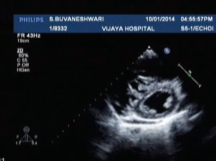

RJM Cardiology Academy Case Discussion AORTIC ROOT DILATATION Management Part 3

Clinical Case Discussion Ventricular Septal Defect VSD Dr Sampath Kumar 15th August 2020

Clinical Case Discussion VHD Aortic Regurgitation VSD 16th Cardiology Update 2020